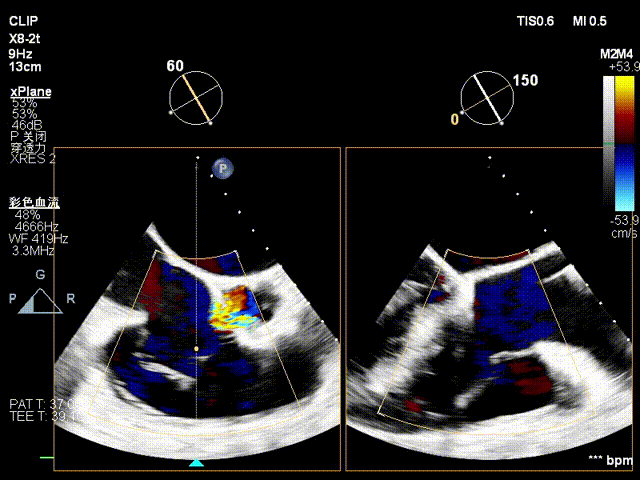

术前超声

术后超声